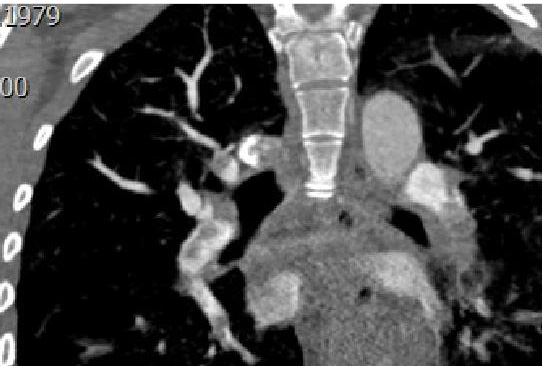

В первые сутки проведён системный тромболизис альтеплазой (рис. 1, 2; табл. 2), через 2-е суток выполнена кроссэктомия в связи с угрозой рецидива ТЭЛА.

Рис. 1. МСКТ-пульмонангиография пациентки B, исходное состояние.

Данные ЭхоКГ и МСКТ пациентки B до и после тромболизиса

Исследование | Исходные данные | Перед выпиской |

Эхокардиография | УЗ-картина острого лёгочного сердца с признаками перегрузки правых отделов сердца: дилатация полости ПЖ, парадоксальное движение МЖП, дилатация НПВ, умеренная лёгочная гипертензия (макс. СДЛА 45–50 мм рт. ст.). Аорта, створки аортального, митрального и трикуспидального клапанов не изменены. Размеры левых отделов сердца, толщина стенок в норме. Глобальная сократительная способность миокарда ЛЖ сохранена, зон нарушения локальной сократимости не выявлено | Гипертрофии миокарда нет. По сравнению с предыдущим исследованием — положительная динамика, уменьшение признаков перегрузки правых отделов сердца, несколько уменьшилась в размерах полость ПЖ, сохраняется парадоксальное движение МЖП, отмечено незначительное уменьшение диаметра НПВ, есть реакция на дыхание, лёгочная гипертензия снизилась до незначительной (макс. СДЛА 35–40 мм рт. ст.) |

Компьютерная томография грудной клетки | Мультифазная МСКТ органов грудной полости с внутривенным болюсным контрастированием: массивная тромбоэмболия в бассейне обеих лёгочных артерий без явных патологических изменений со стороны лёгочной ткани | Значительное уменьшение количества и выраженности дефектов наполнения артериального русла малого круга кровообращения; сохраняются значимые тромбозы обеих нижнедолевых артерий, больше слева. На этом фоне отмечается формирование воспалительных изменений в нижней доле левого лёгкого |

Примечание. ПЖ — правый желудочек; МЖП — межжелудочковая перегородка; НПВ — нижняя полая вена; СДЛА — среднее давление в лёгочной артерии.